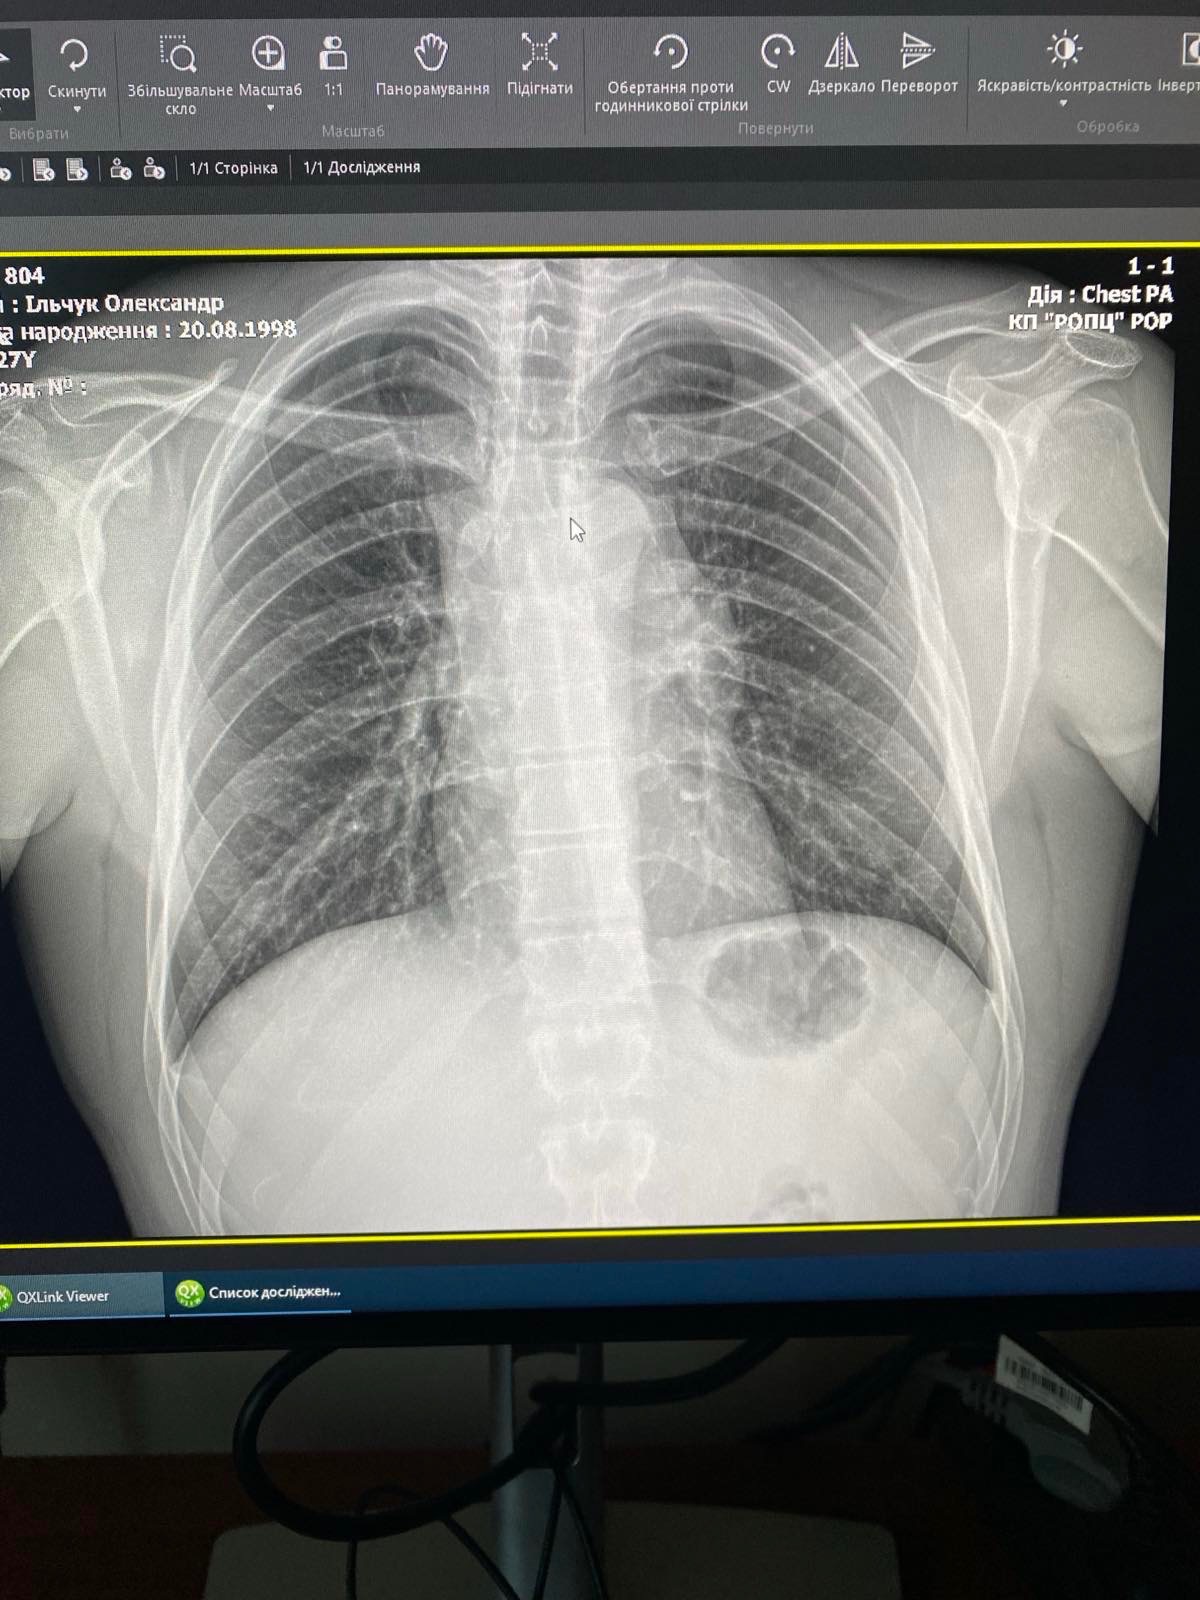

Oleksandr was diagnosed with Primary Mediastinal Large B-Cell Lymphoma, an aggressive but treatable form of cancer. The diagnosis came as a complete shock, especially given his young age and the fact that he was just starting a new chapter of life as a husband and soon-to-be father.

Олександру поставили діагноз — первинна медіастинальна великоклітинна В-клітинна лімфома — агресивна, але лікувальна форма раку. Цей діагноз став повним шоком, особливо з огляду на його молодий вік і те, що він лише починав новий етап життя як чоловік і майбутній батько.